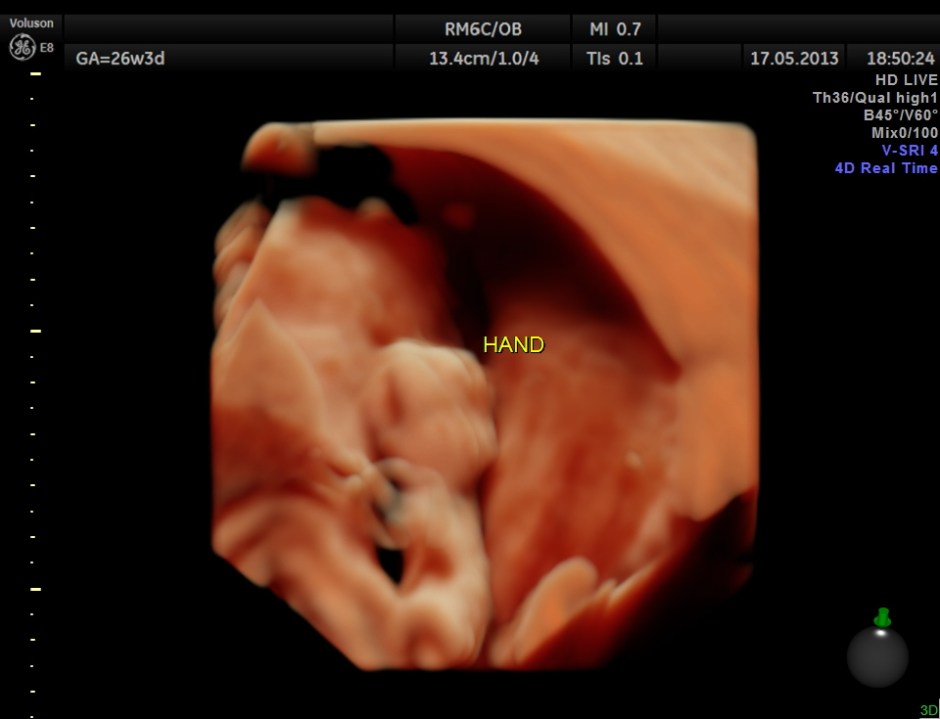

The limbs are shown below.

This fetus did not show any oro-facial clefts ; heart and spine appeared normal.